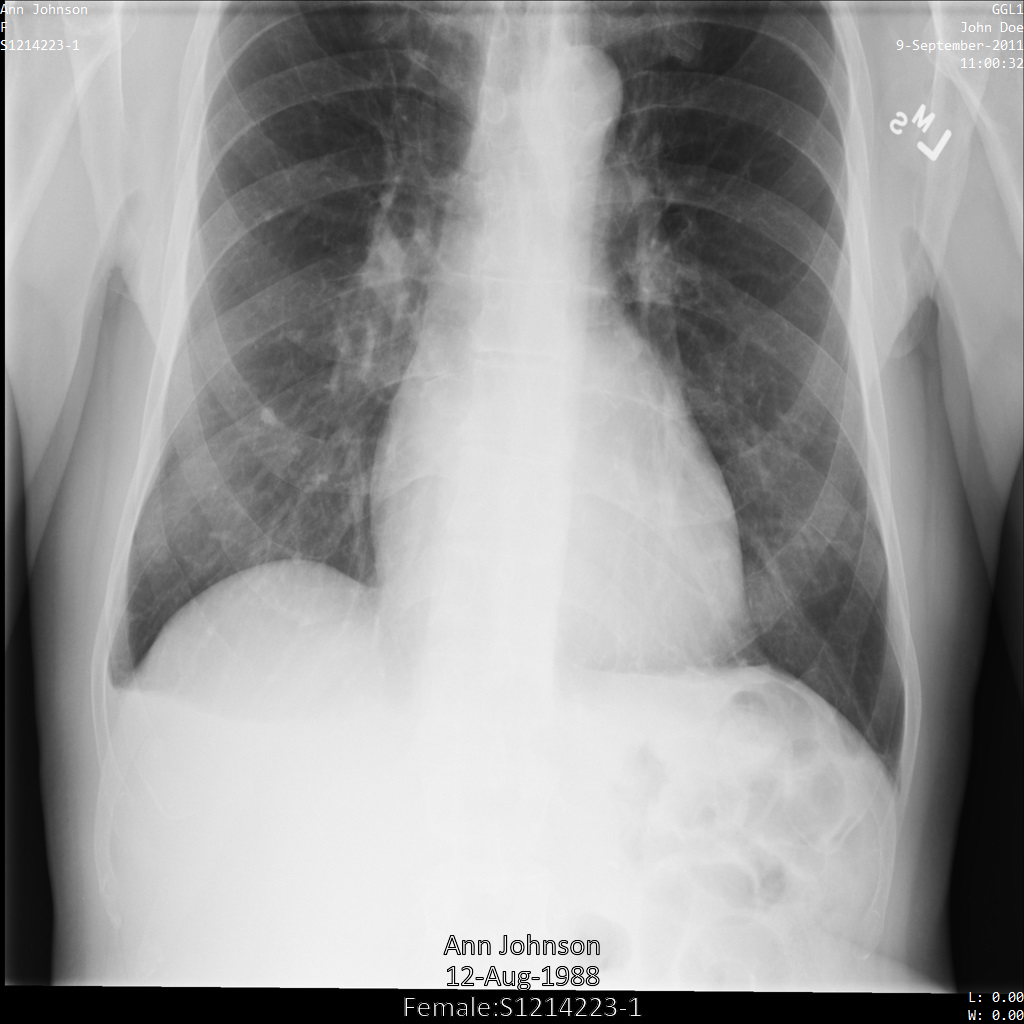

다음 샘플은 태그 필터 프로필 ATTRIBUTE_CONFIDENTIALITY_BASIC_PROFILE을 사용하여 DICOM 저장소 및 DICOM 데이터가 포함된 데이터 세트를 익명화하는 방법을 보여줍니다.

이 태그 필터 프로필은 DICOM 표준의 속성 비밀유지 기본 프로필에 따라 태그를 삭제합니다.

Cloud Healthcare API는 속성 비밀유지 기본 프로필을 완전히 준수하지 않습니다. 예를 들어 Cloud Healthcare API는 태그 작업을 선택할 때 정보 객체 정의(IOD) 제한을 확인하지 않습니다.

ATTRIBUTE_CONFIDENTIALITY_BASIC_PROFILE 태그 필터 프로필을 사용하여 Cloud Healthcare API에 이미지를 제출하면 이미지가 다음과 같이 표시됩니다. 이미지의 상단 모서리에 표시된 메타데이터가 수정되었지만 이미지 하단에 있는 번인 PHI는 그대로 유지됩니다.

번인 텍스트도 삭제하려면 이미지에서 번인 텍스트 수정을 참조하세요.